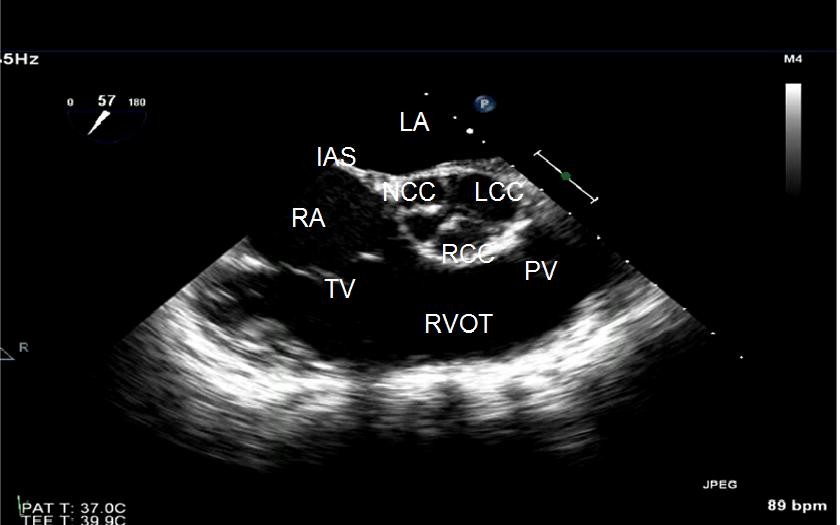

ECHO SERCA przezprzełykowe TEE

Echokardiograficzne badanie przezprzełykowe przeprowadza się w celu dokładniejszego zbadania serca. Dzięki temu, że przełyk przylega bezpośrednio do serca uzyskiwane obrazy są bardzo szczegółowe.